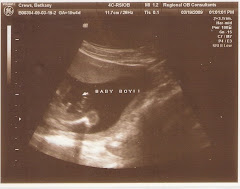

18 1/2 Weeks It's a Boy!!!

This is Baby Crews proving he's a man.